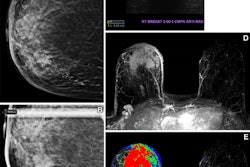

Han and colleagues sought to assess the depth of racial and ethnic minority underrepresentation in neuroimaging research via a study that included 2,464 research articles on Alzheimer's disease brain imaging. Of these, 719 named participant race or ethnicity directly (which the group dubbed "direct studies") and 1,745 culled data from external databases that reported race or ethnicity (which the team categorized as "indirect studies").